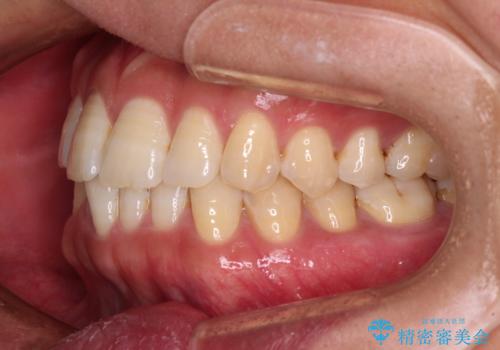

- 前歯のデコボコを気にして来院された患者様です。

インビザラインによるマウスピース矯正も適用となる歯列でしたが、できる限り自己管理の煩わしさのない状態で治したいとのことで、ワイヤー装置にて矯正治療を行うこととしました。

予定していた期間より長くかかりましたが、1年強できれいな歯列に仕上がりました。